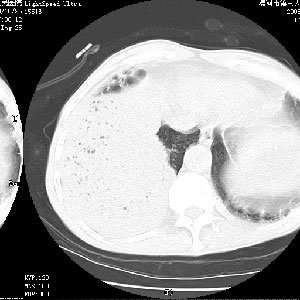

m 老年 发烧、呼吸困难,慢支、肺气肿多年;记的那次是下午大概17:38做的,晚上窒息死亡。

当时我怀疑:1、阻塞性肺不张早期 2、肺脓肿早期,望老师们发表意见

1、右侧脓胸;2、copd;

3、细支气管肺泡癌可以排除,病变以斜裂为界,呈大片状高密度影,内可见多发小气泡,表明有产气杆菌感染所致,内无明显的支气管“枯树枝征”表现,再结合其临床改变(细支气管肺泡癌临表表现重、影像表现轻)所以不符合细支气管肺泡癌(炎症型)的改变。

病变按肺叶分布,病变内可见多个小空腔影,未见充气支气管影,中间段支气管管腔肺窗示密度欠均匀,下肺支气管分叉处基底段支气管隐约可见,未见明显狭窄,中叶支气管通畅,

考虑:阻塞性肺炎伴小脓肿形成可能性大。(痰栓可能性大)

右下肺实变,内有弥漫分面小气泡而无支气管征,叶间裂前移,呈臌大之形,而无收缩之状,兼纵隔稍左行移,故。不支持不张,倒支持大叶肺叶,如楼上所说,小气泡不象残留之肺,不可以考虑产气菌感染吗。

阻塞性肺炎,肺脓肿形成。依据,右下支气管不通,大片实变形内可见小气泡。不支持肺不张。

坠积性肺炎合并右下肺膨胀不全

右下肺阻塞性炎症,内见多发气体影,以肺叶分布.不支持不张.

右肺下叶肺脓肿,右肺下叶支气管痰栓形成。